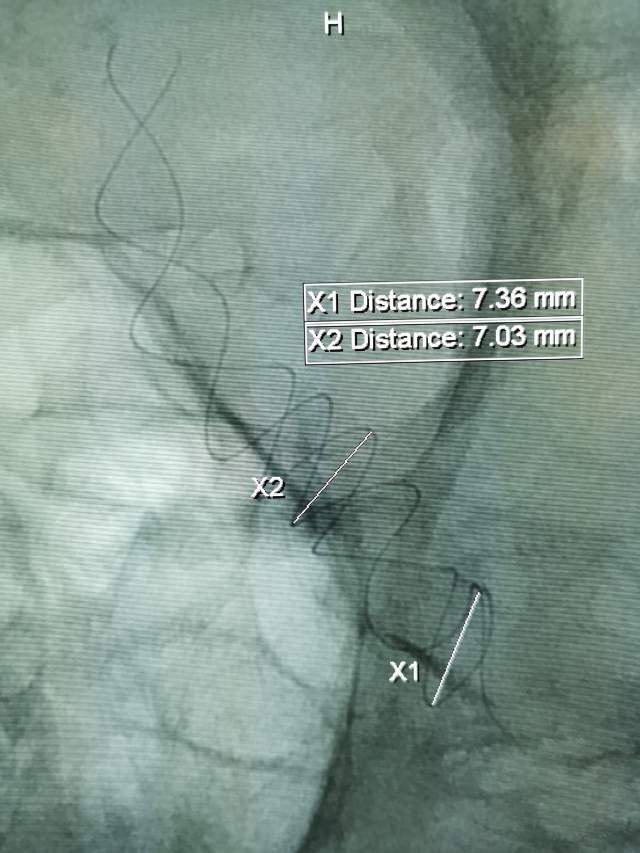

患者男性,34岁,年前自新疆坐车48小时来到我院,诊断:椎基底动脉冗长扩张症,出现脑干压迫症状、后组颅神经症状、部分中组颅神经症状、小脑症状、颅内压增高(220mmHg),症状进行性加重,最大径15mm,血管外面存在血栓造影只能窥见部分,短短两周,病变形态出现明显变化,局部出现明显瘤样凸起(图2-3),手术方案只能临时改变,植入血流导向装置,术后看病人语言、四肢活动均正常,围手术期仍然是一个艰巨的过程,充满了不确定因素,希望患者能安全度过围手术期,早日康复,重返工作岗位~~~